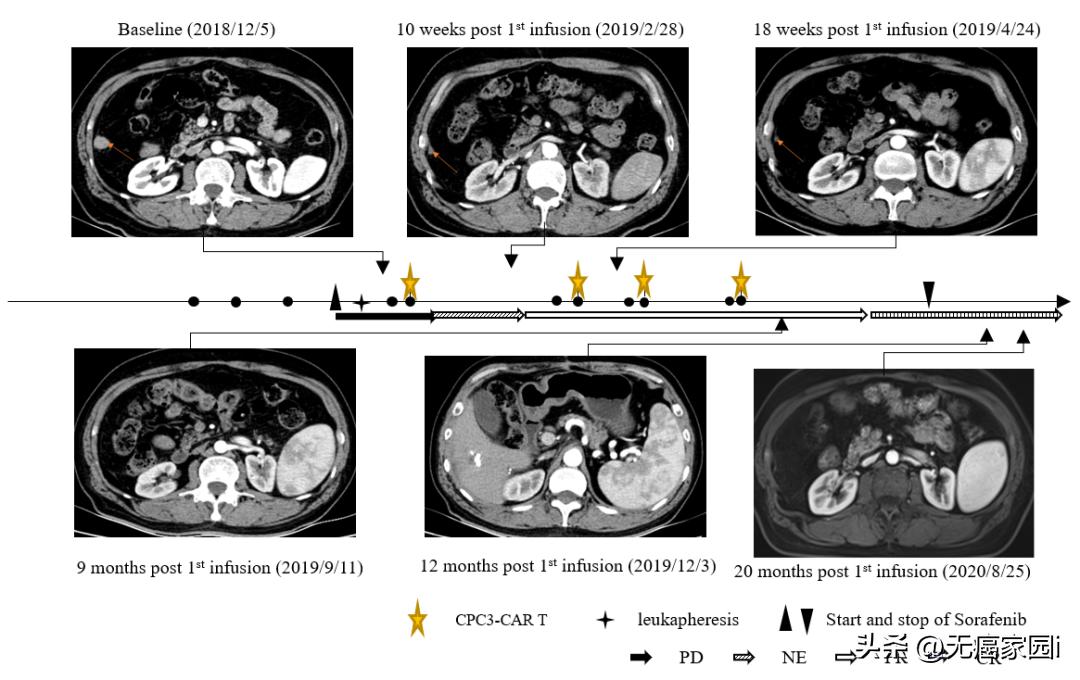

2022年8月18日,科济药业宣布,《Frontiers in Immunology》杂志上发表了关于其自主研发的靶向GPC3的CAR-T细胞候选产品CT011治疗晚期肝细胞癌的长期生存案例报告。

该研究团队是最早报道了GPC3是CAR-T治疗的理想靶点,且率先开展CAR-T治疗肝细胞癌的临床试验。此项研究报道了1名晚期肝细胞癌患者在接受GPC3 CAR-T细胞与索拉非尼联合治疗后获得了完全缓解(CR)和长期生存。

CT011联合索拉非尼治疗耐受性良好。 患者从第3个月开始达到部分缓解(PR), 并 在第一个 CT011 输注周期后的第12个月达到完全缓解 。 肿瘤超过36个月没有进展,在第一次输注后保持完全缓解状态超过24个月。

据悉,这是CAR-T细胞与酪氨酸激酶*制剂抑**联合治疗后报告的首个完全缓解病例。临床结果表明, GPC3 CAR-T细胞与索拉非尼的联合治疗,可能成为治疗GPC3表达阳性的晚期肝细胞癌患者的一种有前景的疗法。